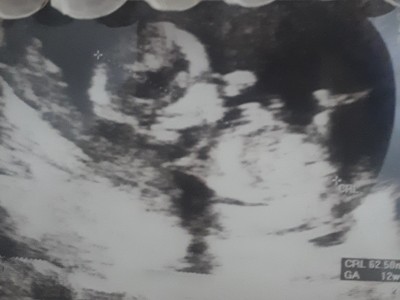

Sizce neye benziyor?

Gebelik haftası 17+2

Kıza benziyor dedi oda ama 12+3te gittim en son kesin birşey söylemedi devlette sürekli göstermiyor diyip duruyor